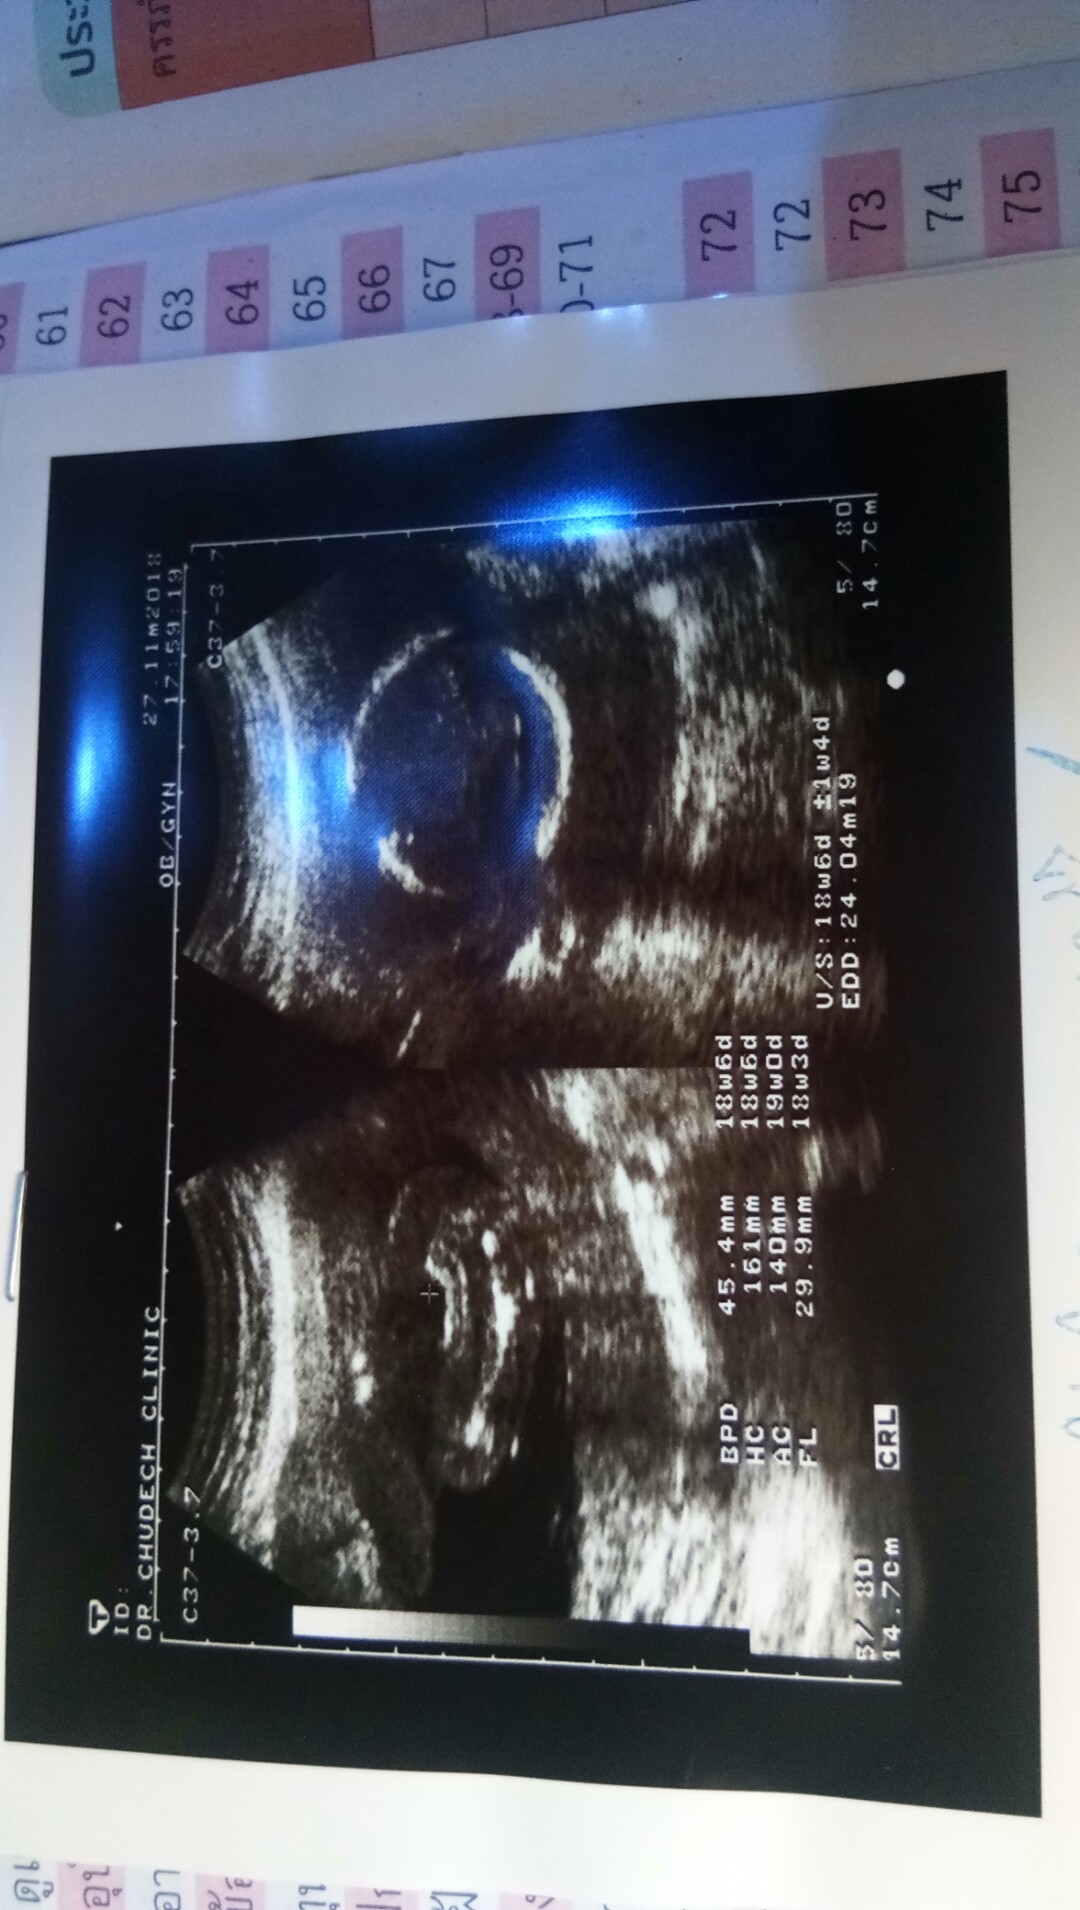

แม่ๆที่เกิดมกรา ได้ลูกสาวขอดูใบซาวหน่อยค่ะ

บ้านนี้หมอบอกว่าลูกสาว แม่ๆว่าใช่ไหมค่ะ ☺️?

บ้านนี้แอบกลัวจู๋โผล่เหมือนกันค่ะ ยังไม่กล้าซื้อของแต่หมอบอกว่า 90% หญิงชัวๆ 😆